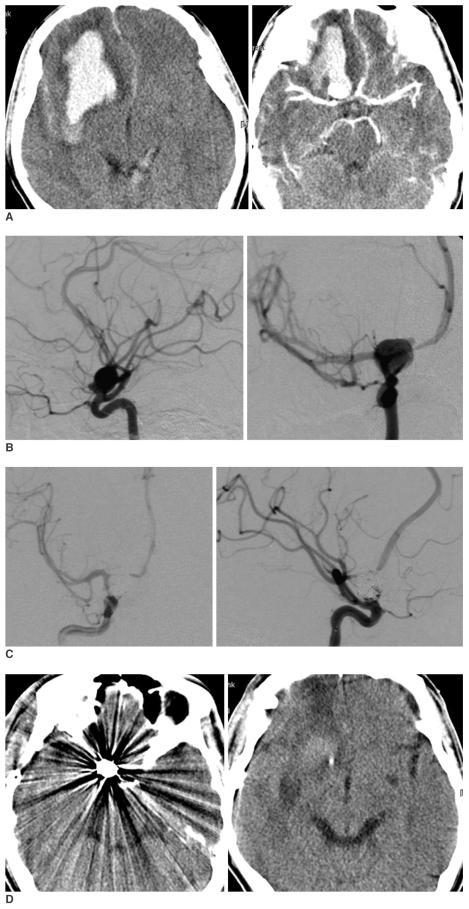

Among 312 patients who were admitted with intracerebral subarachnoid hemorrhage during the recent three years, 119 cases were treated via the endovascular approach. Nine cases were suspected to show aneurysmal intracerebral hemorrhage (ICH) on CT scan and they underwent emergency cerebral angiograms. We performed immediate coil embolization at the same session of angiographic examination, and this was followed by clot evacuation.

Seven cases showed to have ruptured middle cerebral artery (MCA) aneurysms and two cases had internal carotid artery aneurysms. The clinical status on admission was Hunt-Hess grade (HHG) IV in seven patients and HHG III in two. Surgical evacuation of the clot was done immediately after the endovascular coil placement. The treatment results were a Glasgow Outcome Scale score of good recovery and moderate disability in six patients (66.7%). No mortality was recorded and no procedural morbidity was incurred by both the endovascular and direct craniotomy procedures.